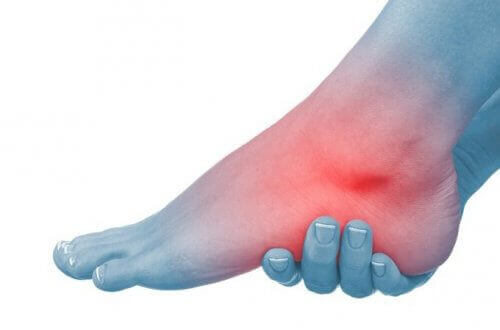

Hvordan artrose i anklene oppstår

Denne typen artrose er forårsaket av progressiv slitasje på brusken i ankelleddet. Det er vanlig at våre ankler blir stive og utvikler deformiteter etterhvert som vi blir eldre.

Klassiske leddhevelser kan også vises, noe som gjør det til en svært smertefull, samt begrenset, tilstand.

Hva er symptomene på artrose i ankelen?

Den første advarselen på slitasje på brusken i dette leddet er smerte når vi går. I begynnelsen legger vi merke til det etter en lang tur.

- Trykk eller mer spesifikk skarp smerte i ankelområdet kjennes når du går, noe som tvinger oss til å hvile anklene i noen minutter for å lindre smerten.

- Senere kan anklene bli hovne, og det kan også være vanskelig å bruke en bestemt type fottøy.